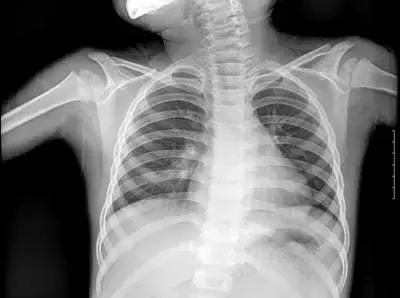

但人体各组织结构的密度不同,X线穿透时被吸收的量不同,就形成了黑白灰分明、层次显著的“片子”。看图举例子:

▲X射线成像图

骨骼、钙化灶、体内液体等(听起来质地较厚重的组织),吸收X光较多,因此形成白色影像,也就是传说中的“高密度影”,上图的上臂、肋骨就是如此。

呼吸道、胃肠道、脂肪组织(听起来质地较疏松),吸收X光较少,在片子上呈现黑色影像,即“低密度影”,图中含气体较多的肺脏是代表。

再就是密度居中的实质器官、 肌肉、结缔组织,比如心室,在片子上呈现的影像介于黑白两色之间。

X光片“泾渭分明”的特点帮医生辨别身体的不同病变。

骨折、肋骨病变,密度高的骨骼白色影像哪里出问题一目了然,比如液气胸等肺部及气道病变,肺脏的黑色影像中就会混入明亮的白色。